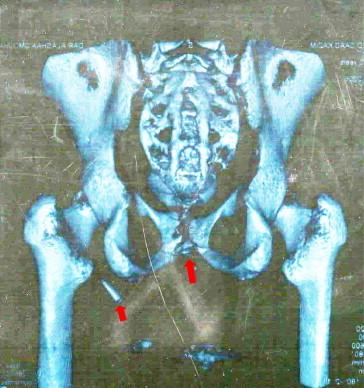

Of 45 patients, 29 (64%) were civilians and 16 (36%) were Iraqi military personnel. The injury was caused by an improvised explosive device (IED) in 25 (56%) patients and by individual firearms in 20 (44%). Of the patients, 24 had penile injuries, 15 had an injury to the bulbar urethra and six had an injury to the posterior urethra. Anterior urethral injuries were managed by primary repair, while posterior urethral injuries were managed by primary realignment in five patients and by a suprapubic cystostomy alone in one. An associated injury to major blood vessels was the cause of death in eight of nine patients who died soon after surgery (P < 0.001).

45例患者中,29例(64%)为平民,16例(36%)为伊拉克军事人员。损伤由简易爆炸装置(IED)导致的有25例(56%),由个人火器导致的有20例(44%)。患者中,24例有阴茎损伤,15例有球部尿道损伤,6例有后尿道损伤。前尿道损伤采用一期修复,后尿道损伤5例采用一期复位,1例仅行耻骨上膀胱造瘘术。9例术后不久死亡的患者中有8例因主要血管的合并损伤死亡(P<0.001)。